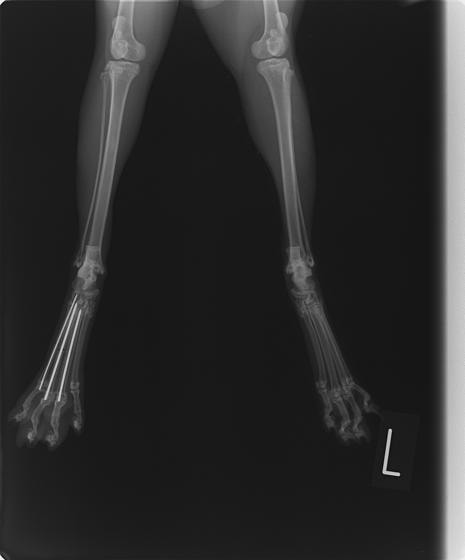

症例3:キルシュナーワイヤーのピンニングによる整復

ペルシャ猫 11ヶ月齢 雄

他院にて左大腿骨遠位の成長板骨折(salter-harrisⅠ型)が認められており、治療相談を目的として来院。当院にて、キルシュナーワイヤーを用いたピンニングにより骨折部位の整復を行いました。術後の経過は良好で、現在も経過観察中です。

術前レントゲン

術後レントゲン

機器

Arthrex社のターゲティングデバイスを用いてピンニングの位置を調整することで、確実な固定を行っています。当院ではこの手術器具以外にも、人の手術にも使用される様々な器具を導入し、手術精度を高め、また医療メーカーと新しい器具の開発、試作にも取り組んでおります。